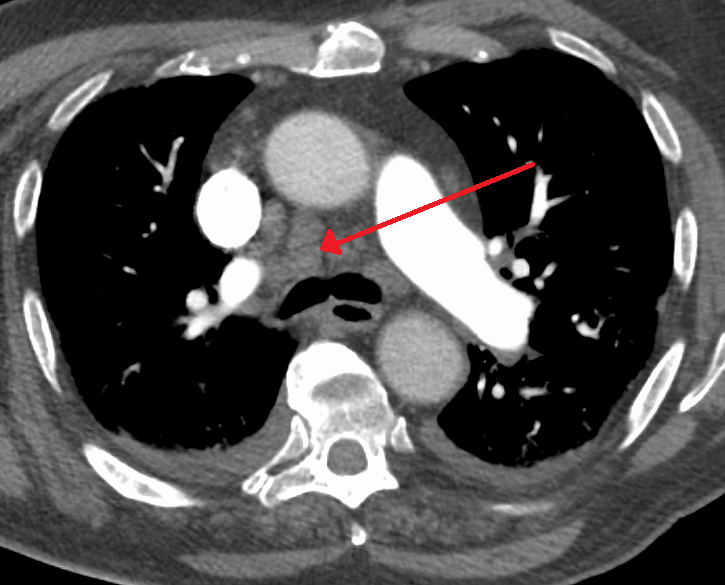

3. 4. 세로칸확장

가슴세로칸확장(widened mediastinum, mediastinal widening) 또는 종격동확장은 가슴세로칸이 기립 PA 흉부 X선에서 너비 6cm 이상 또는 앙와위 AP 흉부 X선에서 8cm 이상으로 나타나는 경우를 말한다.[29]

세로칸확장은 여러 병리를 나타내는 소견일 수 있다.[30][31]

한국에서는 세로칸확장을 동반하는 질환의 발생률이 서구와 다소 차이를 보일 수 있으며, 특히 결핵, 진균 감염 등에 의한 림프절 비대가 상대적으로 흔하게 나타날 수 있다.